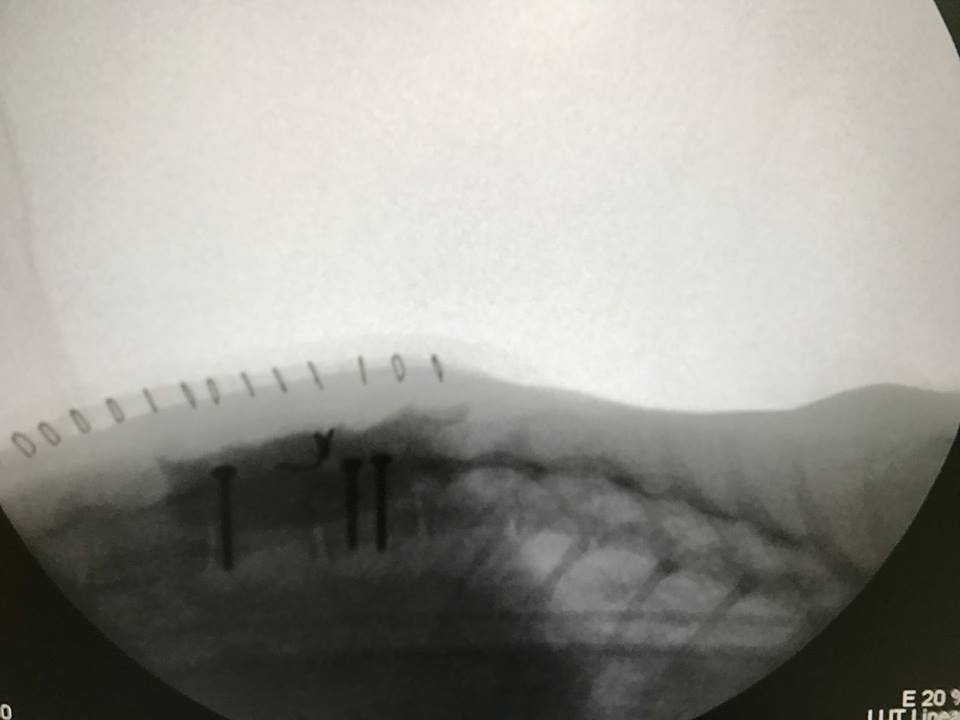

主題: 東湖市場TNR浪貓脊椎骨折手術後復健治療 申請者姓名: lois tsai 花色: 申請日期: 2017-04-16 01:18:27 申請者部落格: 申請者臉書網址: 所在縣市/合作醫院: 台北市/澄諾動物醫院 治療費用: 38300元 需求人數: 40人 已結案 (2024-06-01 13:33:25) 報名人員: We We Lin x2(已付款)、王琇盈(已付款)、Bear(已付款)、Helen Chou(已付款)、Liyin Liao(已付款)、christie(已付款)、Lichen Liao x2(已付款)、Joan Tseng(已付款)、薇薇安(已付款)、Judy(已付款)、Trista Kao(已付款)、黃ㄚ銘(已付款)、黃ㄚ銘(已付款)、Adeline Chen(已付款)、Naommi(已付款)、Diana Ting(已付款)、VICTORIA CHOU(已付款)、張雅筑(已付款)、mavis(已付款)、Midori(已付款)、chucl(已付款)、Anna(已付款)、Lawrence(已付款)、Helen Yu(已付款)、EC(已付款)、Vicky Wu(已付款)、Iris Ji(已付款)、Yi-ling Lu(已付款)、Cherry Wang x2、Cherry Wang x2(已付款)、林小豬(已付款)、HAHA(已付款)、Chihchia Chang(已付款)、小娜(已付款)、Sophia Peng x2(已付款)、Monica Wang(已付款)、Choco Chen(已付款)、 候補人員: 動物病情說明: 東湖市場已TNR兩年的貓咪小恢

在還沒通報醫助前我先帶她到角落動物醫院照X光及血檢確定是脊椎骨折錯位

二月底在台大神經科吳醫師進行手術後已轉往澄諾動物醫院後續治療及復健

在澄諾復健治療一個月後後腳及尾巴已漸漸有知覺及自主動作但小恢背部肌肉還很弱還不能自主排尿需要人工擠尿和積極復健動物近況說明: 已出院接回愛媽家中途早晚幾尿及積極作復健中